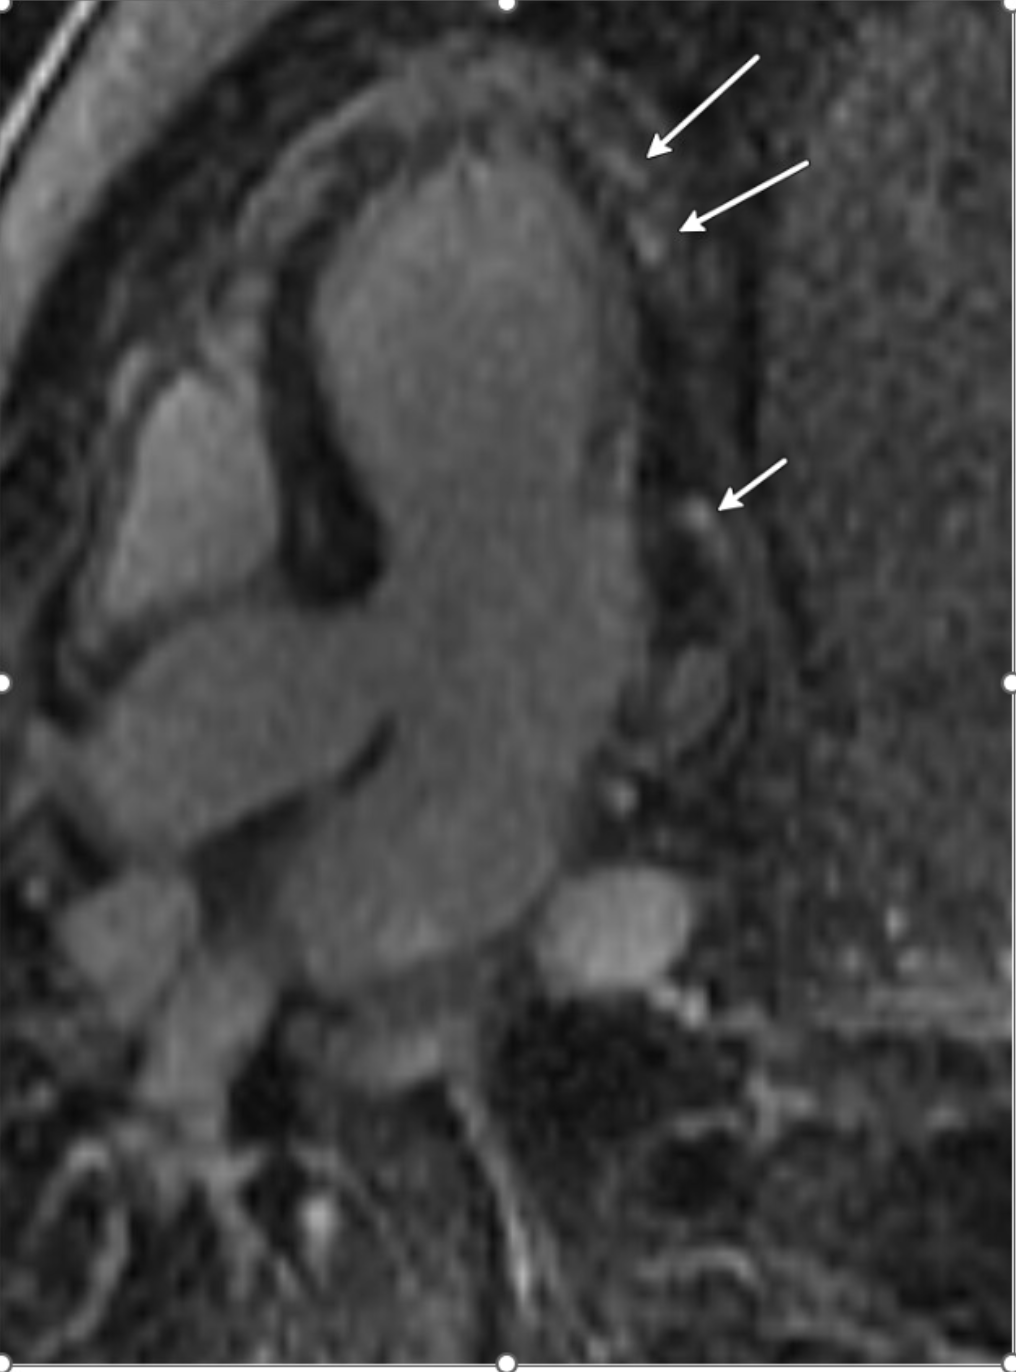

The short Axis LGE demonstrates patchy subepicardial enhancements in the lateral wall of the left ventricle (yellow arrow), consistent with non-ischemic pattern typical of myopericarditis.